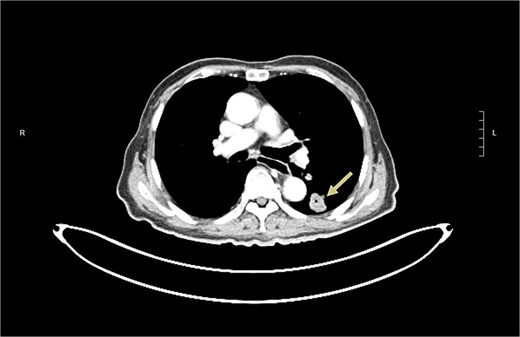

A 74-year-old man who had history of hypertension and diabetes mellitus presented with upper gastrointestinal bleeding. Upper endoscopy revealed deformed pylorus and a 1 cm deep ulcer at anterior wall of first part of duodenum (Fig. 1). Computed tomography (CT) revealed a 4.8 cm exophytic hypoenhancing mass at segment 4a of liver with dilated left intrahepatic duct (Fig. 2). There was aerobilia suggestive of choledochoduodenal fistula. There was also suspicion of diaphragm invasion. Serum carcinoembryonic antigen (CEA) was elevated to 83ug/L while alpha-fetoprotein (AFP) was normal. Both the hepatitis B surface antigen and anti-hepatitis C antibody were negative. Positron emission tomography (PET) confirmed a hypermetabolic liver tumor but no distant metastasis. The clinical diagnosis was ICC with suspected duodenal and diaphragmatic invasion. The patient was offered radical resection for tumor.

CT showing showing an exophytic hypoenhancing mass at left liver with dilated left intrahepatic duct.